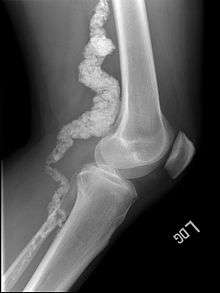

Arterial calcification due to deficiency of CD73 (ACDC) is a rare genetic disorder that causes calcium buildup in the arteries and joints of the hands and feet, and other areas below the waist.[1] Although patients exhibiting these symptoms have been identified as early as 1914, this disorder had not been studied extensively until recently. The identification of the specific ACDC gene and mutations occurred in 2011. ACDC is caused by a mutation in the NT5E gene, which prevents calcium-removing agents from functioning,.[1][2] Patients afflicted with this mutation suffer from chronic pain, difficulty moving, and increased risk of cardiovascular problems.[1][2] In experiments at the molecular level, treatment with adenosine or a phosphatase inhibitor reversed and prevented calcification, suggesting they could be used as possible treatment methods.[1] There is currently no cure for ACDC, and patients have limited treatment options which focus primarily on removal of blood calcium and improving mobility.[1][2]

In ACDC, the gene NT5E, which produces the enzyme CD73, is mutated.[1] A mutation in NT5E causes CD73 to form incorrectly.[1] A nonsense mutation, a single nucleotide insertion, and a missense mutation have all been found to produce essentially the same inactivation of CD73.[1] Normally, CD73 binds to adenosine monophosphate, a nucleotide in DNA, and converts it to adenosine.[1][3][4] In affected patients, little to no CD73 was functional. The calcification of cells is caused in part by a lack of pyrophosphate, which is broken down throughout the body by tissue-nonspecific alkaline phosphatase (TNAP).[1][2] Without pyrophosphate, calcium phosphate crystals cannot be broken down. Since the inactive CD73 is unable to produce adenosine, which inhibits TNAP, there is an increase in TNAP levels and a decrease in pyrophosphate levels.[1][2]